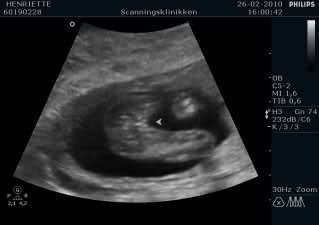

ved den 1. kønscanning var meget 50/50 men ved den 2. kønsscanning i fredags hældte hun meget til dreng og gav det chancen 80/20 i drengs favør. Men hun er usikker pga de to streger der er på billederne som kan være skamlæber men også skygger eller hudfolder

De første 3 billeder er alle uge 15. De to første er dreng og det sidste pige. Det sidste billede er også en pige... Kan derfor godt forstå at hun ikke er helt sikker på kønnet... men tror alligevel jeg tænker dreng

Vedhæftede fotos (klik for at se i fuld størrelse)

men synes vores ikke ligner dit "pige" billed

Jeg synes jeg kan se en sammenligning mellem dit nummer 2 billede og mit nummer 4 billede (som er en pige) og ellers så synes jeg at jeres ligner mest en dreng...